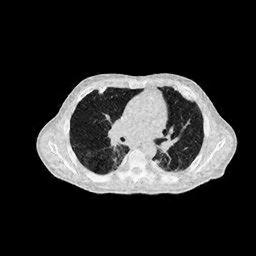

IV-F Real CT Reconstruction

To further verify the effectiveness of the RBP-DIP framework, real CT data from the Finnish Inverse Problem Society [49, 50] was used to validate our algorithm. The few-view and limited-angle reconstruction results are shown in Figure 12. Due to the lack of available training sets, pre-trained models were not included in the experiments. Different from the previous experiment, data from Finnish Inverse Problem Society is highly noisy. However, it is still evident that the RBP-DIP outperforms all other algorithms in all experiments, even under high noise and highly ill-posed conditions.

SNR/SSIM

10.94dB/0.41

13.60dB/0.40

16.25dB/0.53

10.79dB/0.45

13.91dB/0.47

16.49dB/0.57

9.74dB/0.30

12.22dB/0.26

14.46dB/0.42

(a) Reference

8.41dB/0.34

(b) ASD-POCS

12.77dB/0.31

(c) DIP

14.59dB/0.45

(d) RBP-DIP